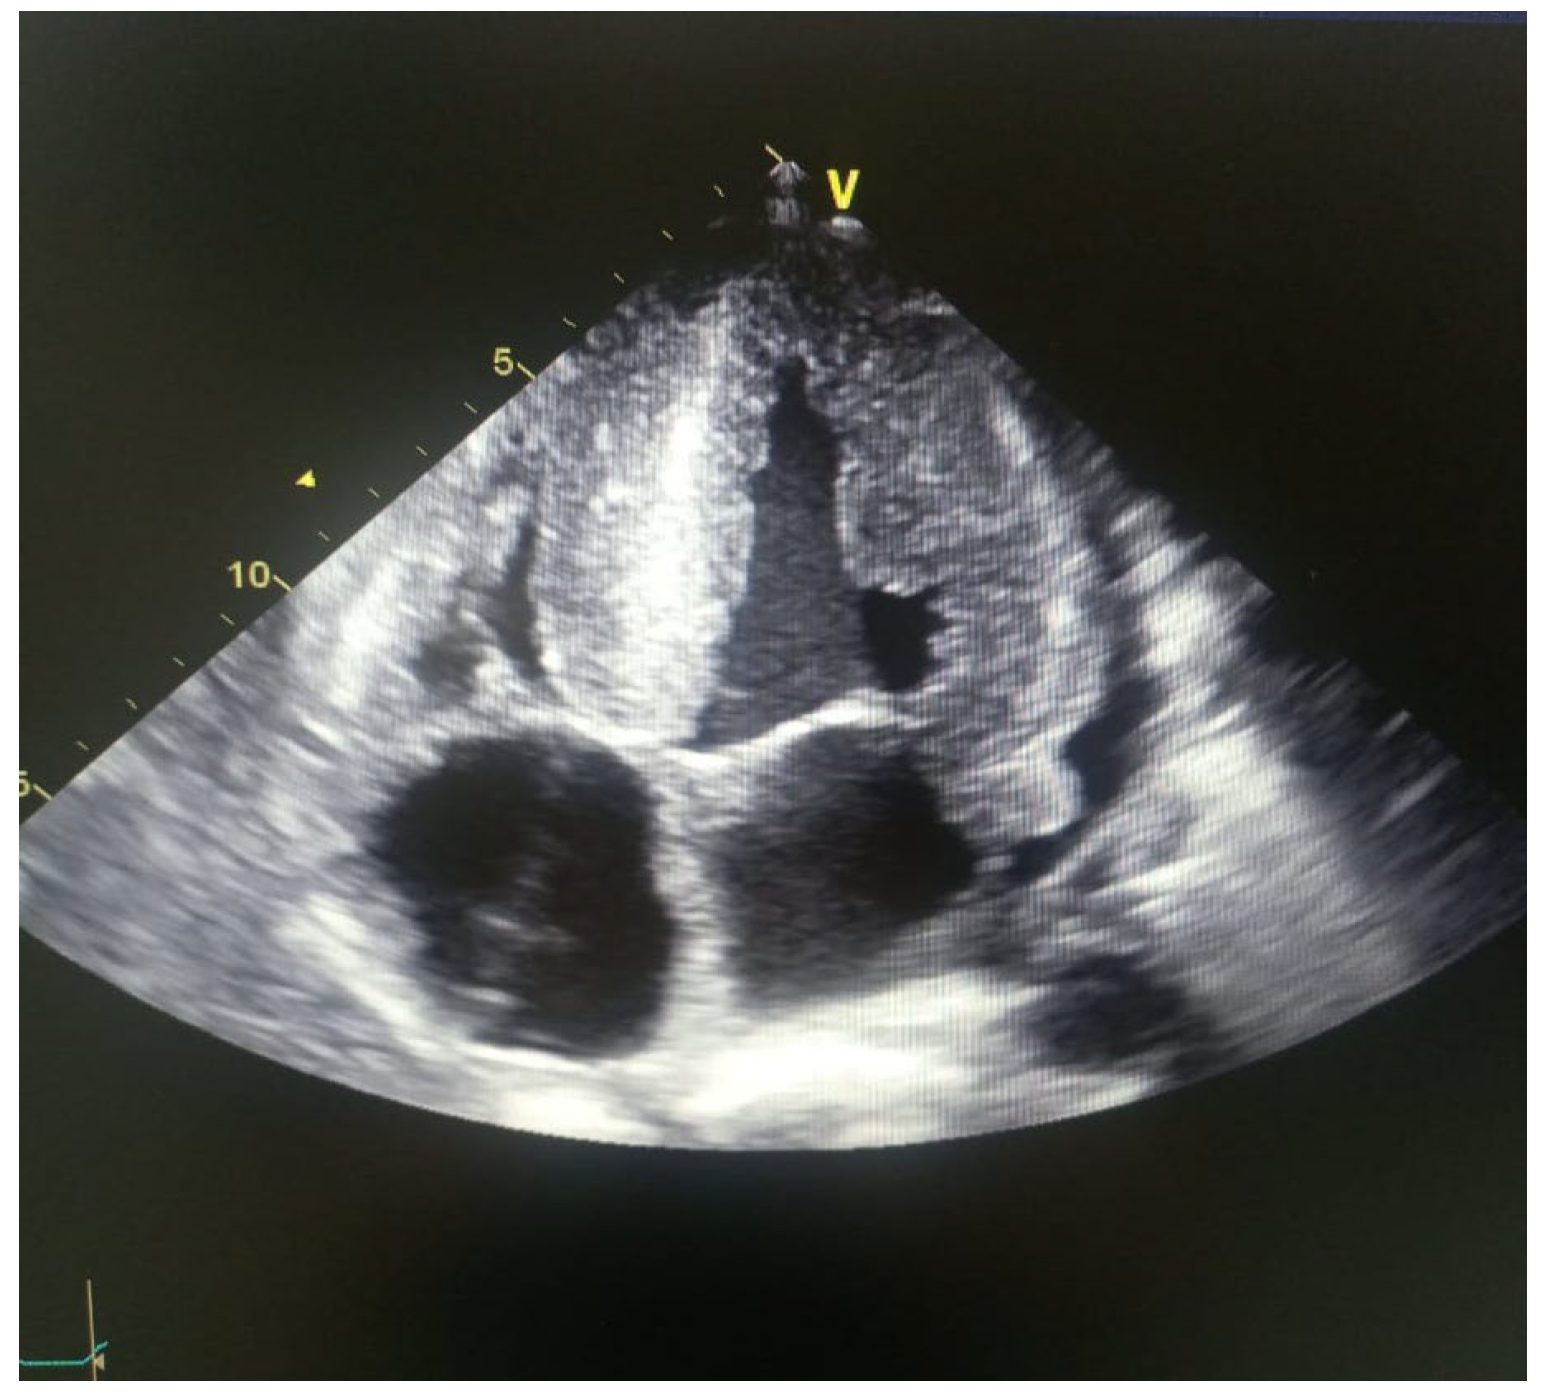

| MYOCARDIOPATHY ON ECHOCARDIOGRAM | Yes | yes | Yes |